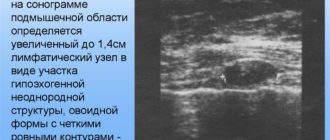

В аксиллярных областях определяются уплотнённые лимфоузлы до 1,3 см

Аксиллярные лимфоузлы: норма, размер, причины воспаления и увеличения, диагностика и лечение Если увеличился аксиллярный